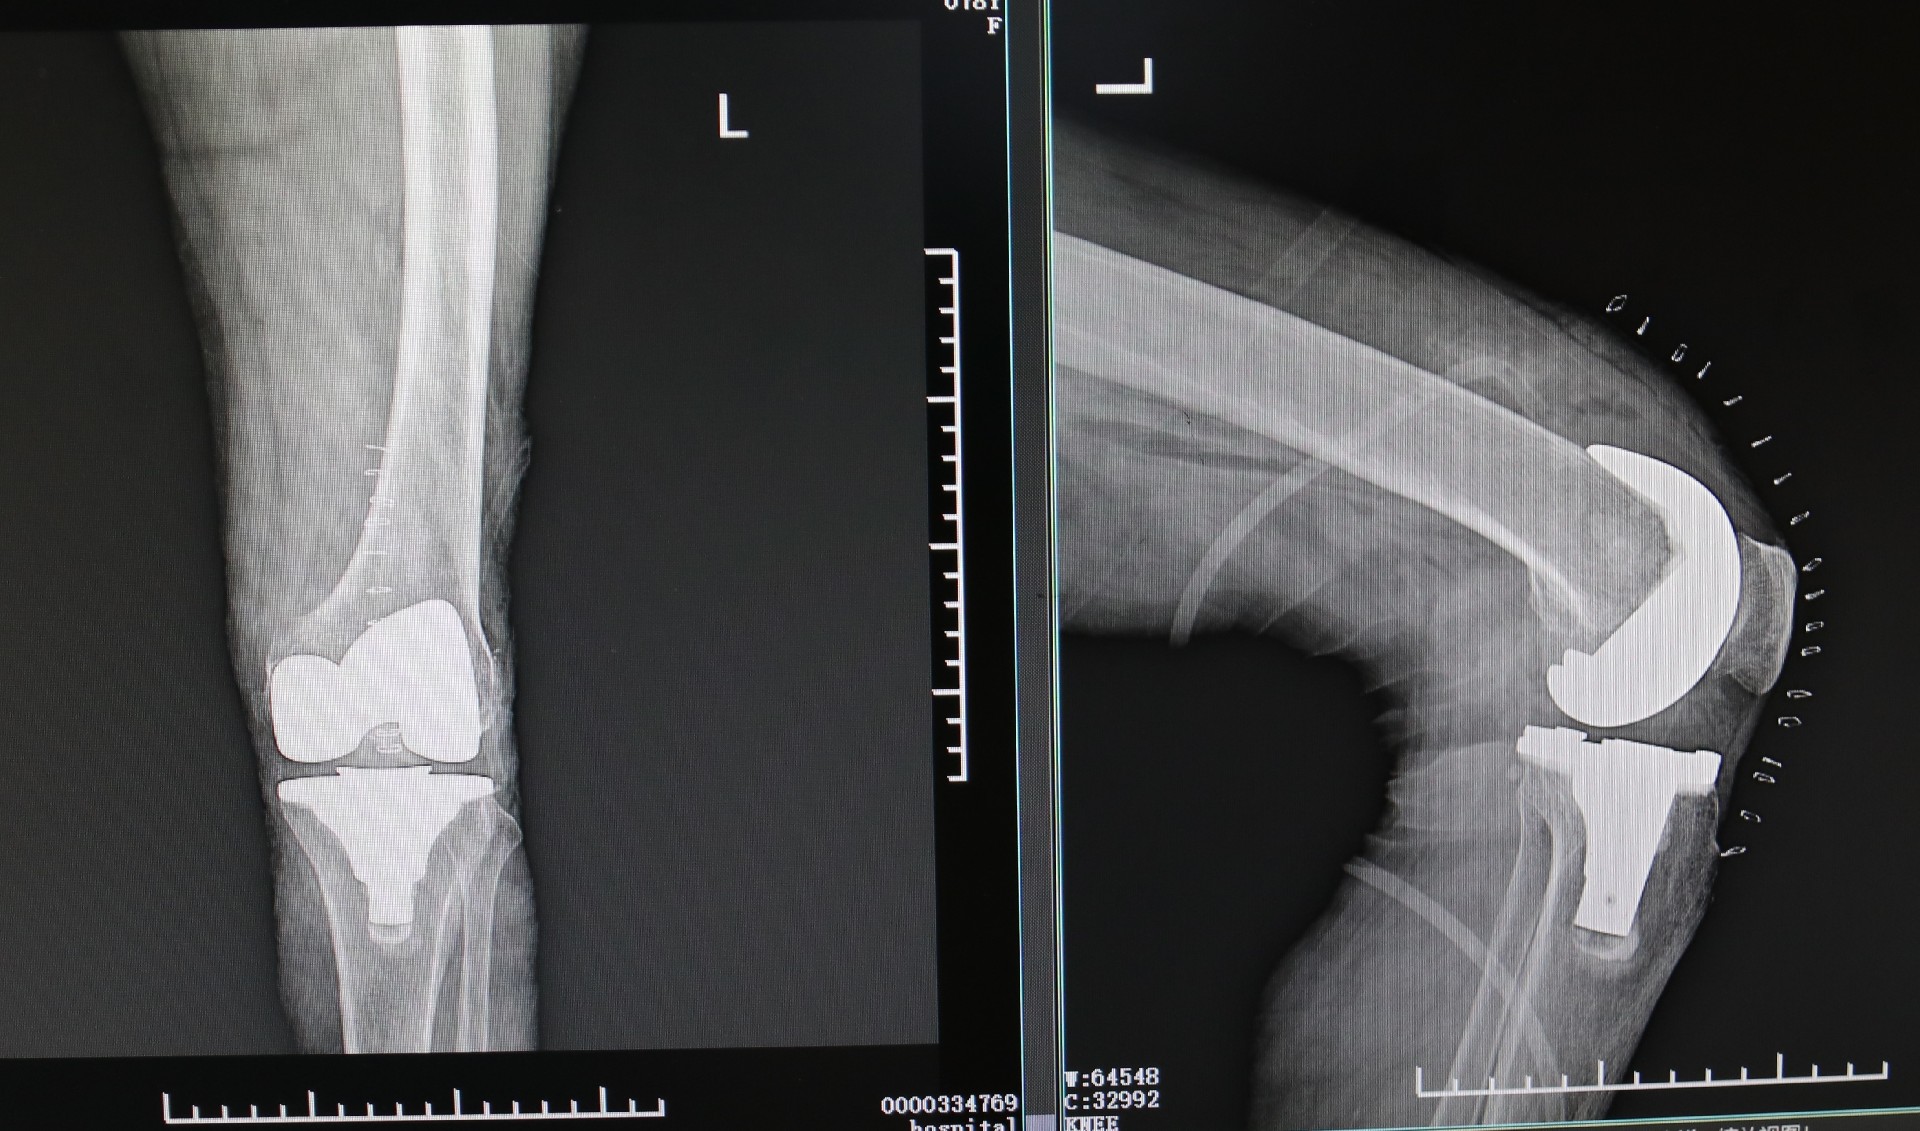

膝关节表面覆盖着软骨,随着年龄的增加,软骨会逐渐磨损,膝关节周围的骨骼、韧带也会发生退变。这使得老人膝盖处骨头间的摩擦加剧,痛苦万分,出现了膝关节疼痛、畸形以及活动障碍等情况。刘海亮主任仔细为老人检查,发现他已是终末期骨性关节炎,保守治疗已经起不到任何效果,针对这类情况,通常考虑进行膝关节置换手术,可有效解决膝关节磨损、矫正变形,并消除患者的疼痛。

很多患者担心,膝关节置换是不是把整个膝盖都换掉?其实不然,膝关节置换手术是将不光滑的地方“修平”,然后加上一个“托”,中间再加一个高分子材料制成的垫让变得狭窄的关节间隙重新获得“空间”,形成没有摩擦或摩擦力很小的膝关节屈曲伸直装置。完善术前准备,老人的膝关节置换手术成功完成,老人的新生活也即将开始。